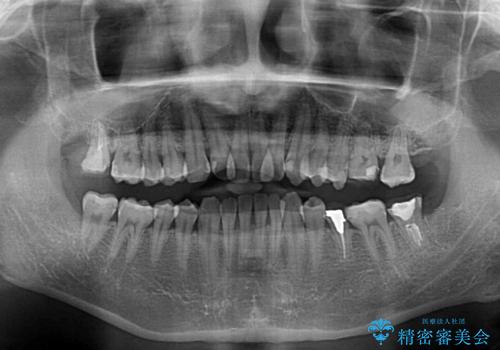

- 虫歯が多く、セラミッククラウンにより虫歯治療を行っている途中で矯正治療をしたいとのことで来院された患者様です。

上顎前歯が舌側に転位しており、なるべく早く楽に矯正したいとのことで、ワイヤー矯正を行うこととしました。

虫歯治療途中の歯は仮歯が装着されていたため、そのまま矯正治療を行い、矯正後に補綴治療を行うこととしました。